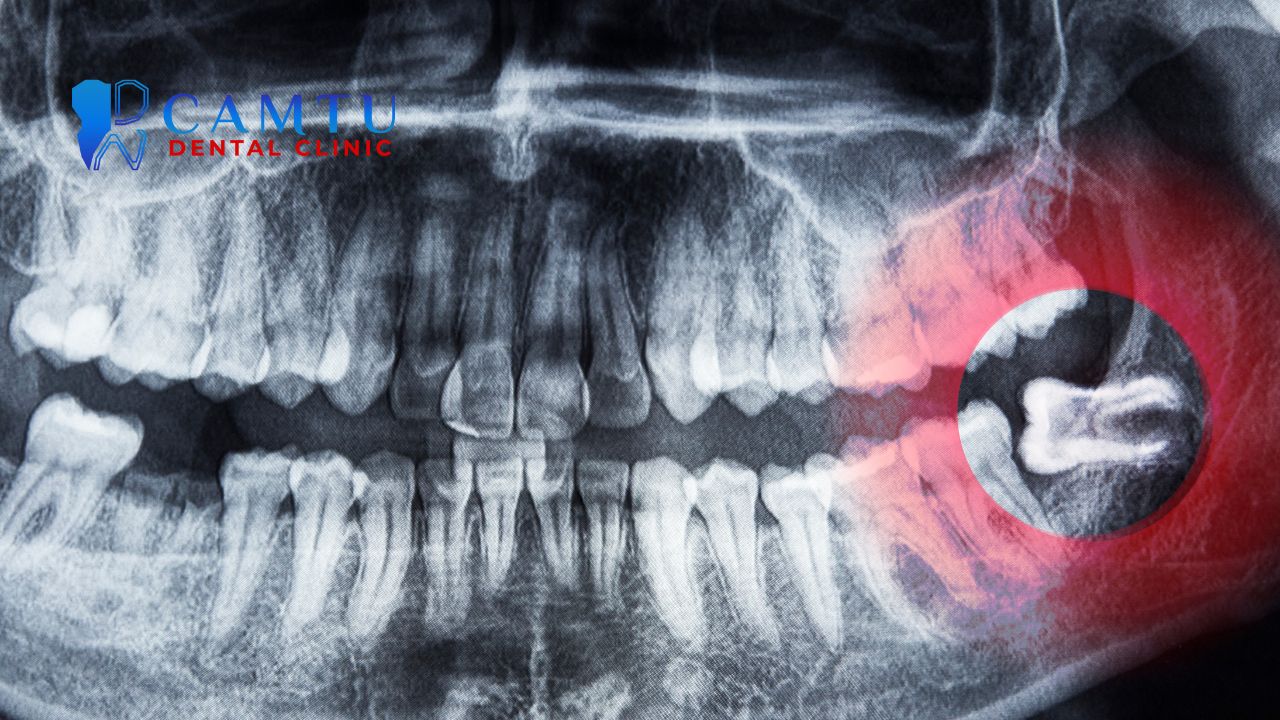

- Khám và chụp phim X-quang: Để đánh giá chính xác vị trí, hướng mọc và mức độ phức tạp của răng khôn trước khi nhổ, từ đó giảm nguy cơ biến chứng sau khi nhổ răng khôn.

Ngoài ra, răng khôn nằm gần dây thần kinh hoặc xoang hàm trên có thể làm tăng nguy cơ tổn thương thần kinh hoặc thủng xoang. Những trường hợp này cần được đánh giá kỹ bằng phim chụp trước khi nhổ răng.